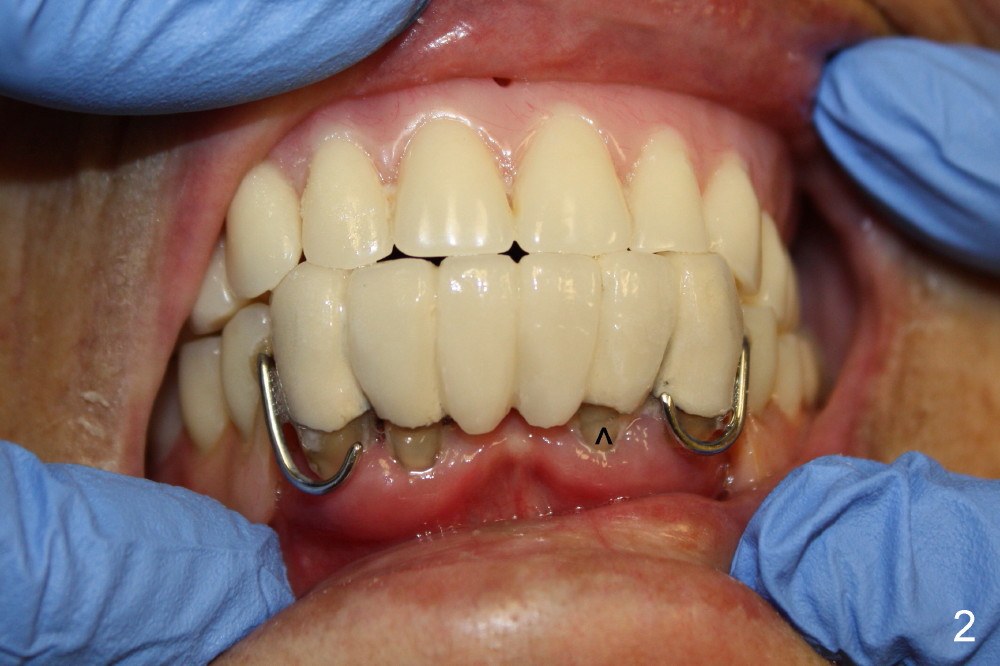

Mrs. Chen, 74 years old, cannot eat properly, because the lower anterior bridge is loose (compare Fig.1 (normal bite) and Fig.2 (edge to edge with lower partial in)). All of these four abutment teeth may have root fracture (Fig.2 >, Fig.4,5). The ridge in the posterior area (Fig.3 black arrows) is much narrower than that of the anterior area (red arrows). The traditional complete denture should have poor retention shortly after anterior tooth extraction with atrophy of the alveolus. Treatment plan is to fabricate the lower immediate complete denture, extract the four remaining teeth (#22,23,26,27), place four immediate implant with ball attachment, and reline the denture with soft reliner initially and retain it with O rings once the implants are osteointegrated.

Since there is limited space between the lower lateral incisor and the canine, implants to be placed should not be too big. For example, if the diameters of the implants at the sites of #22 and 23 are 5 and 4 mm, respectively, there is less than 2 mm of bone between the implants (Fig.5). It is not safe. The bone may die.

It is safer if the diameters are reduced to 4.5 and 3.5 mm, respectively (Fig.4), as recommended by Dr. Borgner as follows. In fact, the implants for the lateral incisors are one piece, whereas those for the canines are two pieces.